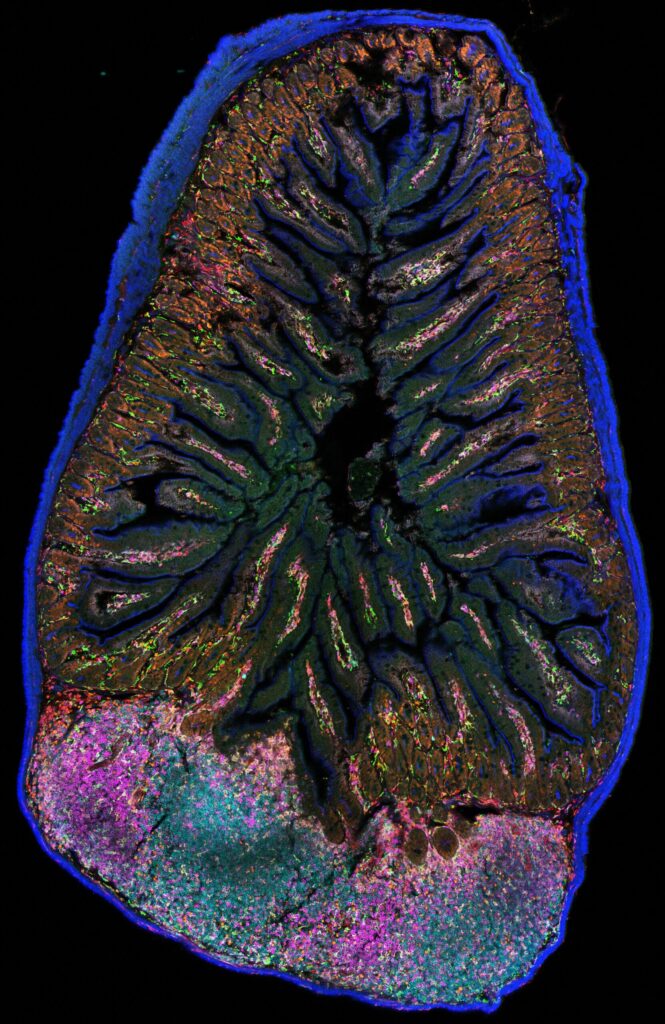

Explore the endless possibilities of microscopy through the 2025 FBI digital calendar!

Once again this year, the participants in the France-BioImaging Image Contest have outdone themselves, providing us with stunning microscopy images captured using a variety of techniques. These images also showcase the diversity of models and applications, highlighting the many possibilities offered by microscopy. Take a look at 12 of the 37 images submitted to the France-BioImaging Image Contest 2025!

A big thank you again to all the participants!

FBI Image Contest 2025

Once again, we were delighted by the diversity of submitted images, showcasing a wide range of microscopy techniques, models and applications. This competition highlights how microscopy images can also take on an artistic and creative dimension, revealing the beauty of the invisible world.

The winners were:

1st place: Nicolas Barois with Gut Flower-Flora

2nd place: Vishwadeep Mane with The Puzzled Awakening

3rd place: Simli Dey with Kaleidoscope

A recent research project led by Margaux Delaporte, Céline Raguénès-Nicol and Michel Samson (collaboration between Irset Institute and H2P2 platform) has introduced a new imaging protocol to explore the immune microenvironment of human hepatocellular carcinoma using multiplex immunofluorescence. Let’s take a closer look!

Understanding tumor heterogeneity through the immune microenvironment

Hepatocellular carcinoma (HCC) is characterized by pronounced intra- and inter-tumor heterogeneity, which represents a major challenge for the development and efficacy of targeted therapies. The immune microenvironment plays a central role in disease pathogenesis and in the response to treatment. Gaining a better understanding of this complexity requires approaches that can identify immune cell populations, their functional states, and their spatial organization within tumor tissue.

A multiplex immunofluorescence strategy based on Cell DIVE

In this study, Delaporte et al.1 present a multiplex immunofluorescence (mIF) protocol based on the Cell DIVE technology, enabling the simultaneous detection of multiple protein markers on a single section of human hepatocellular carcinoma. The aim of this approach is to perform detailed immunophenotyping of the tumor microenvironment while preserving tissue architecture.

Cell DIVE relies on successive cycles of immunofluorescent staining, high-resolution image acquisition, and chemical inactivation of fluorochromes. Images from each cycle are aligned using nuclear DAPI staining as a common reference and assembled to generate a final multiparametric image of the entire tissue section. Image analysis is performed using open-source tools, notably QuPath, for cell segmentation and phenotyping.

A multiparametric view of the tumor immune ecosystem

The protocol is based on a 20-marker panel combining cellular positioning markers, structural markers of normal and pathological liver tissue, vascular markers, and markers identifying major myeloid and lymphoid populations. Markers of lymphocyte activation, exhaustion, and immune checkpoints are also included to explore the functional status of immune cells within the tumor microenvironment.

This approach enables the generation of a multiparametric, single-cell-resolution spatial map of the immune microenvironment in HCC from a single histological section. It allows the spatial distribution of immune cells and their relationships with tumor and vascular structures to be investigated, while remaining compatible with human samples commonly available in translational and clinical research. The authors also indicate that the methodology can be applied to the study of liver immune infiltration in other pathological contexts and adapted to tissues beyond the liver.

Example of final mIF image of human hepatocellular carcinoma whole slide. For visualization purposes, only 5 markers are displayed: WGA (yellow), CD4 (orange), CD20 (green), CD31 (red), CD68 (blue) and DAPI (gray). Scale bar represents 2 mm.